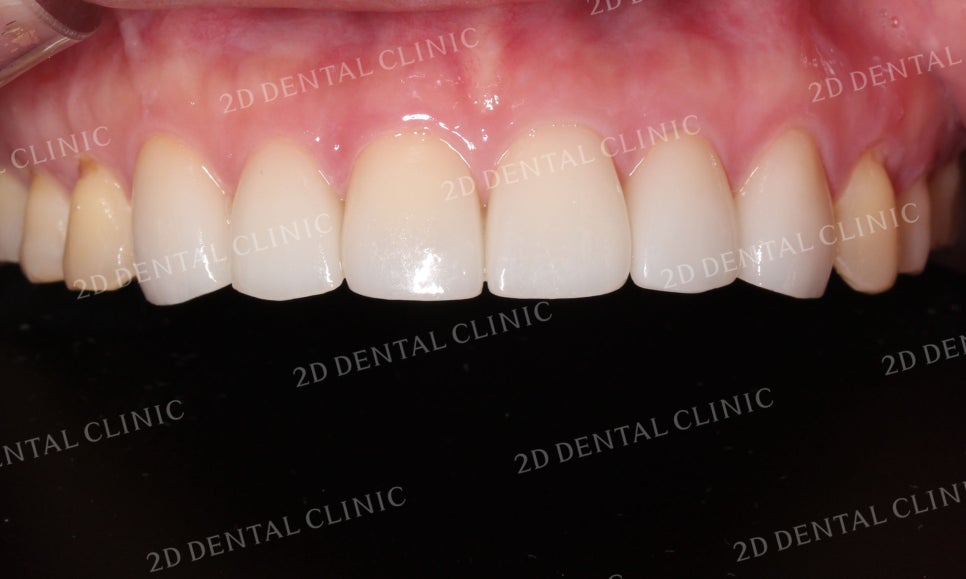

상악 전치부의 사진입니다.

환자분께서는 상악에 총 6개의 블링스를

부착하셨는데요,

블링스 시술 전 중절치 쪽의

잇몸이 후퇴하여 뿌리가 드러나

블랙트라이앵글이 생겼습니다.

그러나 전치부 6개의 블링스 시술 후

블랙트라이앵글은 물론

누렇게 착색되었던 치아의 색상도

밝은 상아색으로 돌아온 모습입니다!